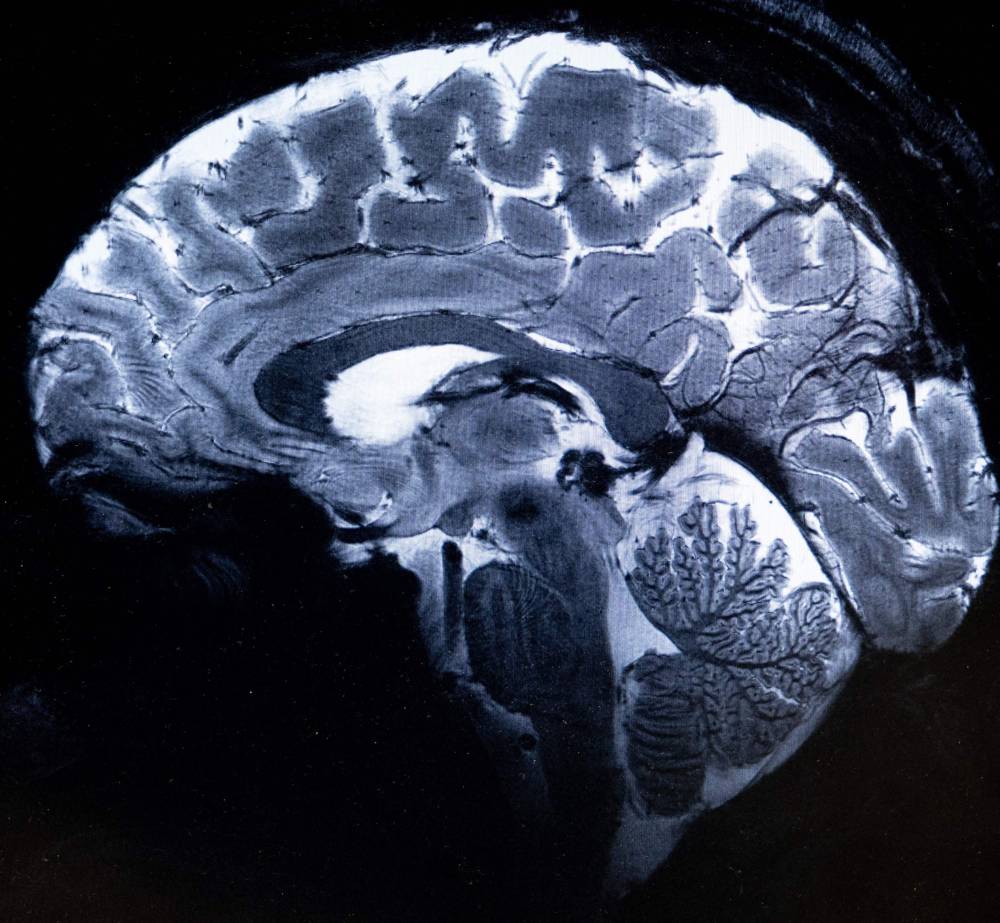

SACLAY - The world's most powerful MRI scanner has delivered its first images of human brains, reaching a new level of precision that is hoped will shed more light on our mysterious minds -- and the illnesses that haunt them.

This power allows the machine to scan images with 10 times more precision than the MRIs commonly used in hospitals, whose power does not normally exceed three teslas.

On a computer screen, Vignaud compared images taken by this mighty scanner, dubbed Iseult, with those from a normal MRI.

"With this machine, we can see the tiny vessels which feed the cerebral cortex, or details of the cerebellum which were almost invisible until now," he said.